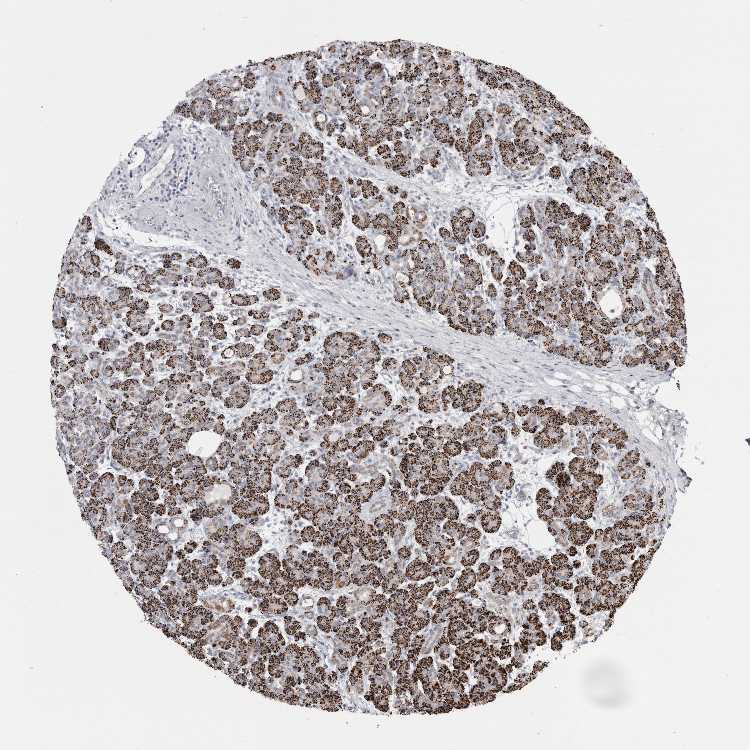

PANCREAS - Antibody stainingi

Antibody staining in the annotated cell types in the current human tissue is reported as not detected, low, medium, or high, based on conventional immunohistochemistry profiling in selected tissues. This score is based on the combination of the staining intensity and fraction of stained cells.

Each image is clickable and will lead to virtual microscopy that enables deeper exploration of all samples and also displays staining intensity scores, fraction scores and subcellular localization as well as patient and tissue information for each sample.

Antibody HPA026077

Exocrine glandular cells High

Pancreatic endocrine cells Not detected